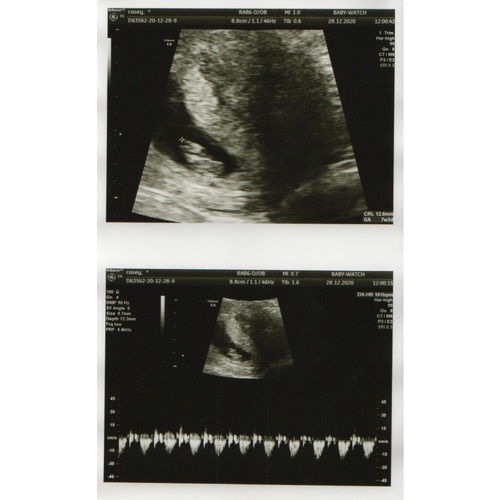

Hier was ik 7w3d. Het hartje zagen we al kloppen.